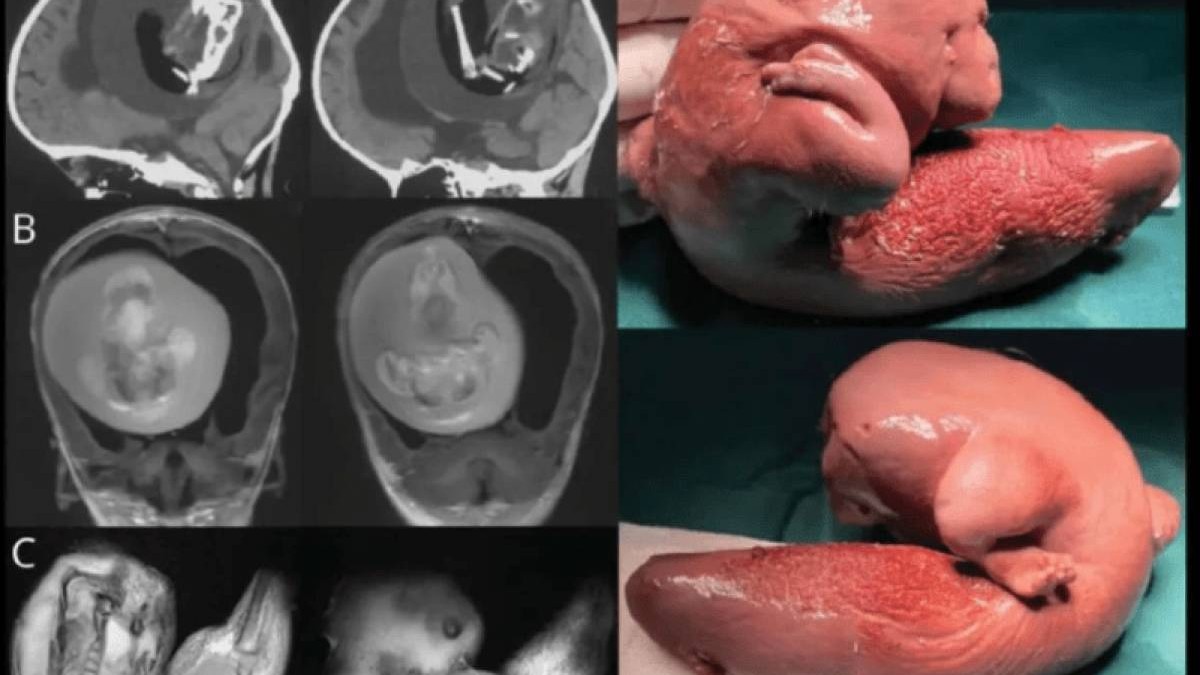

Қытайлық хирургтар бір жасар қыздың миынан егізінің ұрығын алып тастады деп хабарлайды Kznews.kz ақпарат агенттігі Gazeta.ru сайтына сілтеме жасап.

Қыздың ата-анасы баланың басы үлкейіп, моторикамен қиындықтары пайда болғанын байқап, ауруханаға апарады. Нәтижесінде оның миында 10 см-лік ұрық бар екені анықталды.

Дәрігерлердің айтуынша, ұрық өсіп, аяқ-қолдары мен сүйегі, тіпті тырнақтары өскен. Бұл ұрық қан айналым жүйесі мен қыздың қан айналым жүйесінің бірігуіне байланысты болуы мүмкін.

Медицинада “ұрық ішінде ұрық” деген термин бар. Бір ұрық екіншісінің денесінде өседі. Әлемде 200-дей осындай жағдай орын алған. Ұрық ауыз қуысы, жамбас, ішек жолдарында анықталады. Осы уақытқа дейін 18 адамның миында егіз ұрық табылды. Нәрестелерден бөлек, тіпті ересек болған кезде де бұл анықталып жатады.